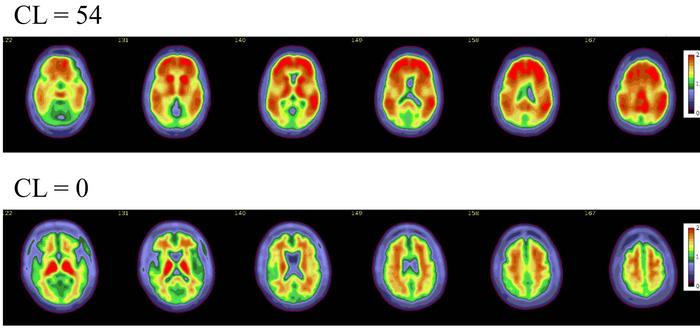

Axial color scales images of two brains show examples of an amyloid positive scan with a higher centiloid (CL) number and more red colors compared to a normal scan with normal background binding of the amyloid tracer signifying no amyloid plaques.